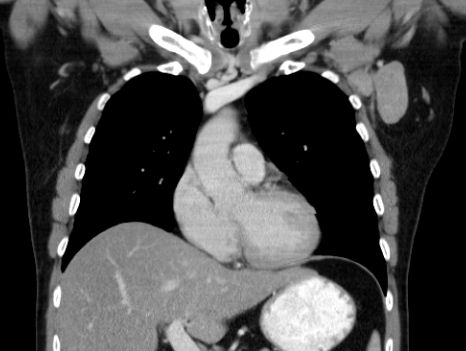

| thorakal | 21-jährige Frau mit Morbus Hodgkin mediastinal und zervikal beiderseits. Stadium IIA, Risikofaktor: hohe BSG. Noduläre Sklerose. | ||